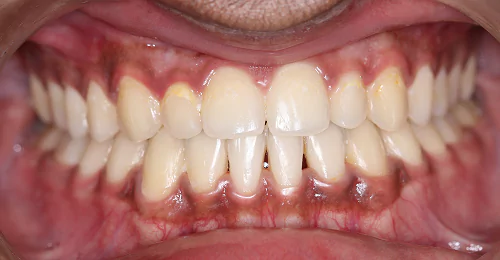

Anterior Crossbite Correction

Without Extraction Of Teeth

A young newly married female had crossbite in front teeth and when she smiled she felt her teeth appeared crooked. Being newly married she also had concerns regarding wearing braces. Assessing the situation, we advised ceramic braces and treated the condition without extracting or removing any teeth.

Pre Treatment

The treatment was completed successfully after a period of 18 months. Our patient is now embarked on her newly married life with more confidence.